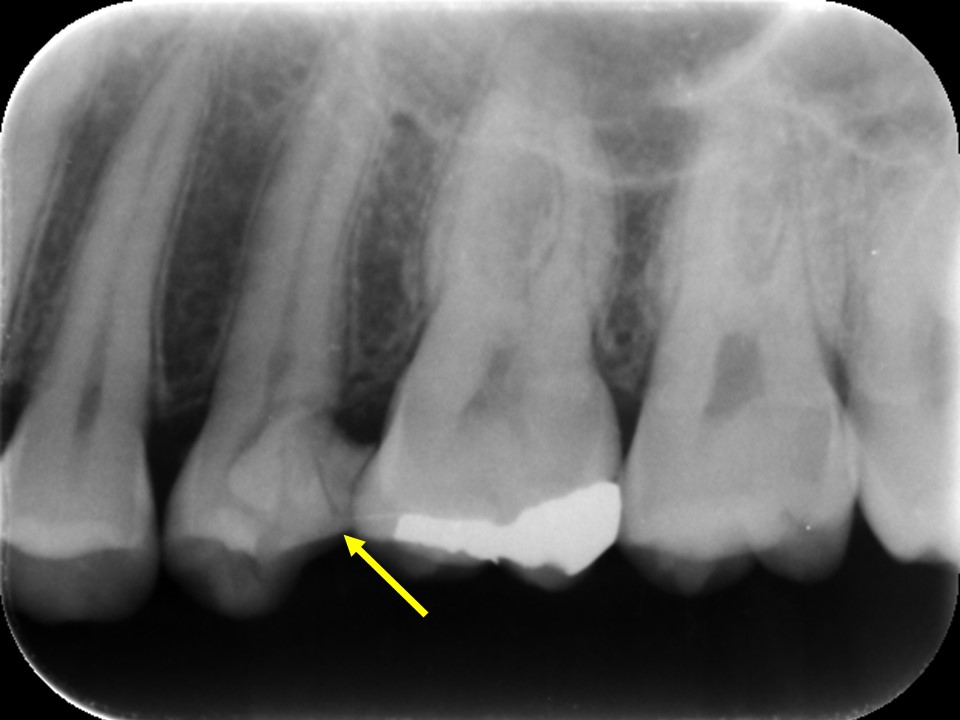

レントゲン写真では、歯間部に大きなコンポジットレジンが詰めてあり、ほぼ歯髄に達していました(下写真)。症状とレントゲン画像から、不可逆性の急性化膿性歯髄炎と診断し、抜髄を行う必要があると判断しました。

治療前のレントゲン画像です。

ほぼ歯髄に達するコンポジットレジン充填が施してあります(矢印)。

痛みが出ても何ら不思議な状態ではないです。